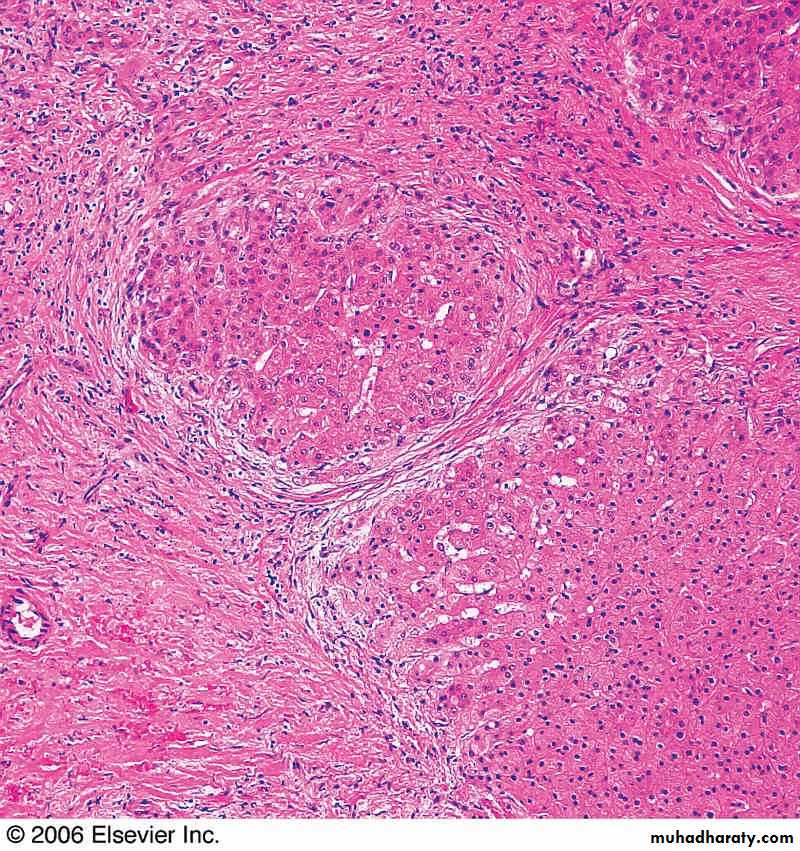

Focal Nodular Hyperplasia: Subcapsular solid mass with central scar, composed of the normal components of liver lobule

Central portion of nodular hyperplasia showing the interphase between the fibrous scar and the hepatocytic nodules.